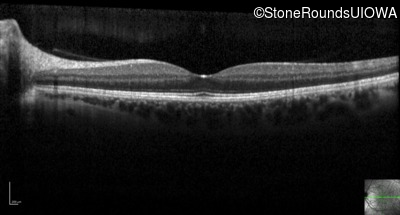

Optical Coherence Tomography - Right - 20/16 -1

Exemplar / OCT Stack